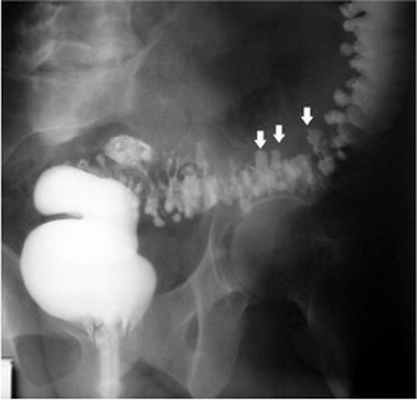

В диагностике заболевания вне осложнений наиболее ценными являются рентгенологические (ирригоскопия с ирригографией) и эндоскопические (ректороманоскопия, колоноскопия). Таким образом, возможность проявления тяжелых осложнений требует своевременной диагностики и лечения дивертикулярной болезни.

Наилучшим методом обследования при подозрении на воспаление дивертикулов является компьютерная томография. При этом исследовании вокруг человеческого тела вращаются несколько излучателей и получаются многочисленные рентгеновские изображения. Затем компьютерная программа по этим фрагментам создает цельные «срезы» тела. Томография позволяет не только увидеть изменения контура кишечной стенки (то есть собственно дивертикулы), но и изменения тканей, окружающих толстую кишку (например, абсцессы). Менее точным способом найти дивертикулы является ирригоскопия или, по-простому, клизма с сульфатом бария, который хорошо различим в рентгеновских лучах и позволяет увидеть внутренний контур кишки и некоторые совсем уж грубые осложнения (например, стриктуры).